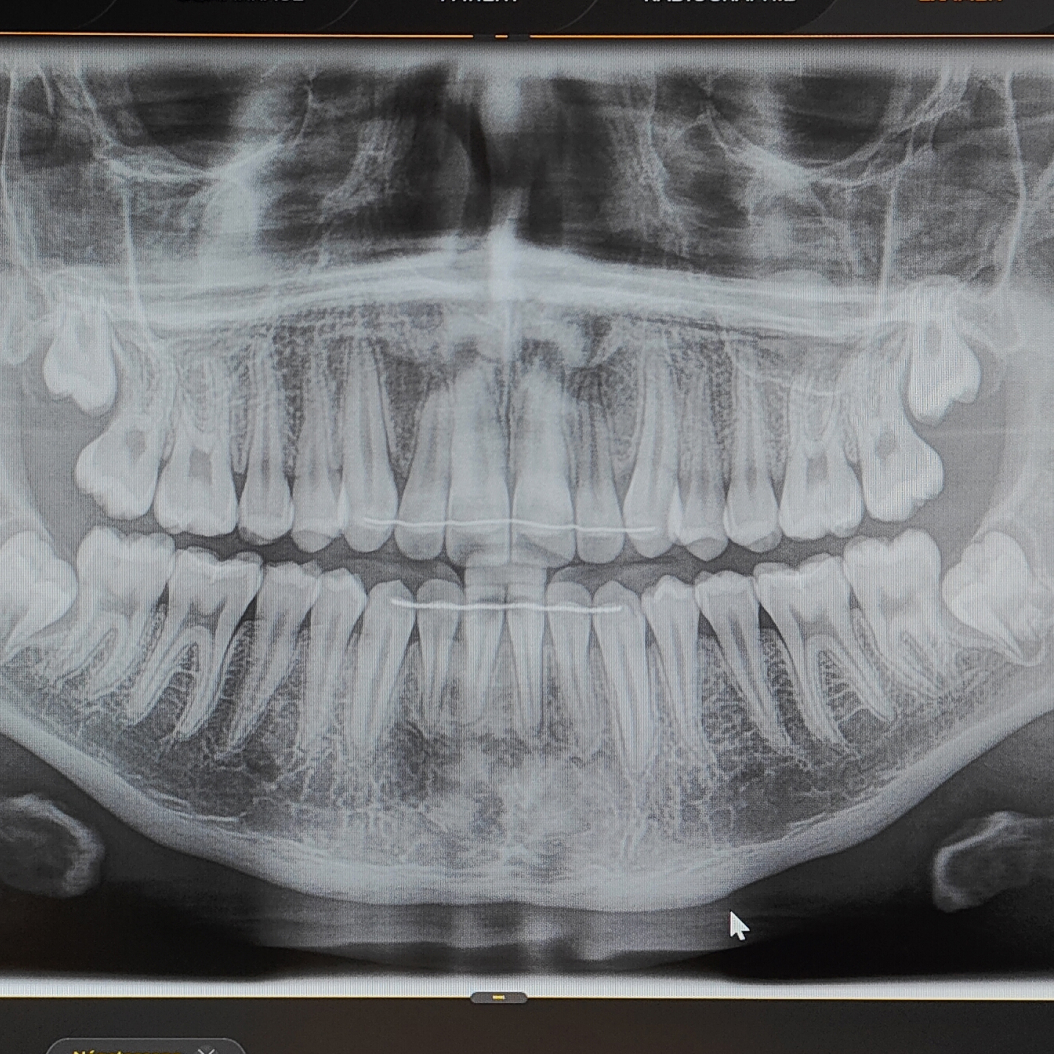

Nous veillons à l’ensemble de votre santé bucco-dentaire grâce à un examen minutieux des dents, de la langue, des gencives, du palais, de l’intérieur des joues et des tissus mous afin de détecter diverses anomalies. Nous pouvons dépister plus de 200 affections de la cavité buccale et reconnaître les liens entre la santé de la bouche et certaines douleurs ou maladies systémiques.

Examen bucco-dentaire complet

La base de notre pratique générale réside dans un examen dentaire complet. Le Dr Lévesque se fait un devoir de dresser un portrait fidèle de votre condition buccale. Cet examen est primordial à tout âge indépendamment de votre acuité en matière d’hygiène buccale.

L’examen bucco-dentaire complet consiste en une inspection visuelle en plusieurs points, notamment :

Le dentiste peut également examiner la région du cou (glandes et ganglions) et demander des radiographies.

Lors de l’examen, nous sommes en mesure de détecter diverses anomalies :

Suivant l’examen complet, vous obtenez un diagnostic précis et un plan de traitement personnalisé pour améliorer votre santé bucco-dentaire dans l’immédiat et à long terme.